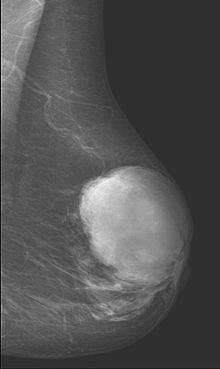

Phyllodes tumor in mammography

This is predominantly a tumor of adult women, with very few examples reported in adolescents. Patients typically present with a firm, palpable mass. These tumors are very fast-growing, and can increase in size in just a few weeks. Occurrence is most common between the ages of 40 and 50, prior to menopause. This is about 15 years older than the typical age of patients with fibroadenoma, a condition with which phyllodes tumors may be confused. They have been documented to occur at any age above 12 years.